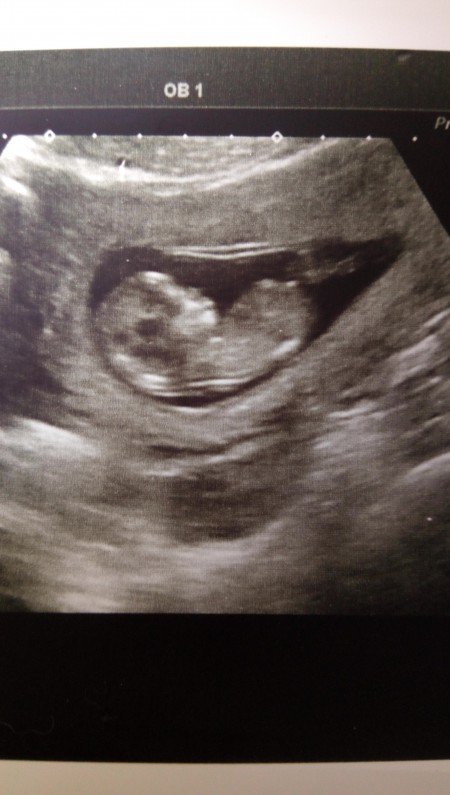

arkadaşlar cinsiyet tahmini şimdiden yapılır mı 13+1 im

Gebelik haftası 13+1

Cinsiyet bacak arasından gozukur burada yan duran bir bebek var dolayisiyla gorunmez suan kaldi ki doktor da gorse soylerdi canim bu sekilde bakarak anlasilmaz

Bi parlaklık var ama göbek kordonu o sanırım bacak arası karanlık çıkmış bişe demek çok zor

kiza benziyor canim